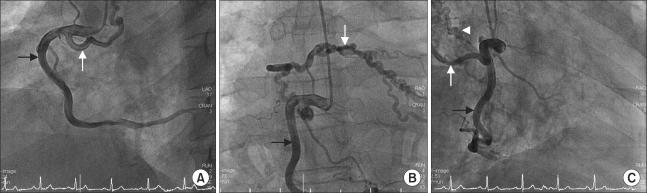

A coronary-bronchial artery fistula is a very rare congenital anomaly of the coronary artery whose etiology and pathogenesis have not yet been clarified. Most patients with coronary-bronchial fistulas are asymptomatic; however, some patients present with congestive heart failure, infective endocarditis, myocardial ischemia induced by a coronary steal phenomenon, or rupture of an aneurysmal fistula. Furthermore, patients with a coronary-bronchial artery fistula rarely manifest life-threatening hemoptysis due to the associated bronchiectasis. We report herein the case of a patient with a coronary-bronchial artery fistula who had bronchiectasis and a history of massive hemoptysis and myocardial ischemia.

https://cdn.ncbi.nlm.nih.gov/pmc/blobs/cb71/3283785/279b477f2c30/kjtcs-45-49-g001.jpg